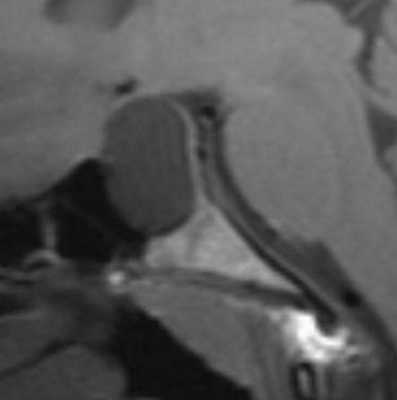

Вестибулокохлеарный нерв (VIII) состоит из 4 пучков. Опухоли происходят обычно из вестибулярной его части. Шваннома - инкапсулированная доброкачественная (градация 1) опухоль, происходящая из дифференцированных неопластических шванновских клеток оболочек периферических нервов. Невриномы ММУ составляют около 3% опухолей головного мозга. Часть шванном (двухсторонние слуховых нервов) связана с НФ 2 типа. Пик частоты между 40 и 60 годами. Растут медленно и крайне редко малигнизируются. Клинические проявления связаны с нарушением функции нерва и компрессией ствола. Шваннома может происходить из любого отрезка по ходу нерва и хорошо прослеживается при МРТ области ММУ. Невринома видна как на Т2-взвешенных, так и на Т1-взвешенных МРТ в виде округлого образования. Невриномы хорошо и равномерно усиливаются после МРТ с введением контрастного вещества. Невриномы области цистерны могут иметь компонент во внутреннем слуховом проходе, особенно, хорошо видимый при МРТ головного мозга с контрастированием. Изредка встречаются невриномы полностью расположенные внутри канальца. Они составляют наибольшую диагностическую сложность при МРТ, требуют тонких срезов и контрастирования. Менингиомы ММУ обычно типично расположены и при МРТ имеют характерную форму и типичные черты при МРТ с контрастированием. Однако редко встречаются внутриканальцевые менингиомы. При МРТ они неотличимы от неврином. Холестеатомы при МРТ имеют смешанную интенсивность сигнала, в зависимости от их содержимого. На диффузионно-взвешенных МРТ холестеатомы обычно яркие.

МРТ головного мозга. Аксиальная Т2-взвешенная МРТ. Фрагмент ММУ. Холестеатома слева.